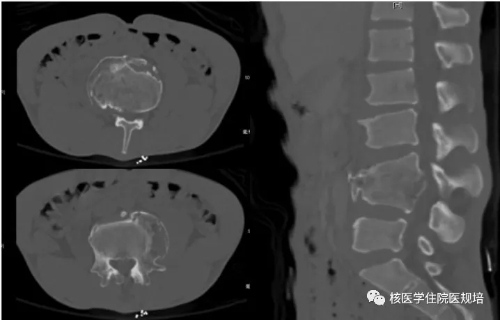

患者男性,30岁, 3个月前无明显诱因突发大小便失禁,同时伴下肢活动障碍,为进一步诊治就诊于我院。既往史:出生后诊断为先天性无痛无汗症,其他无特殊病史。查体:患者轮椅进入病房,神志清楚,对答切题;全身皮肤干燥、见多处瘢痕,皮肤痛觉缺失,指甲发育不良,脊柱生理屈度存在,无明显棘突压痛。双上肢未见明显畸形,肌力、肌张力未见明显异常。左下肢可见膝关节不规则隆起,表面不光滑,质硬,无波动感,关节屈伸正常,局部皮温正常,无皮肤红肿、破溃或静脉怒张,压痛(-);右下肢未见明显异常。双下肢感觉较弱,巴氏征(-)。实验室检查无明显异常发现。腰椎X光片及CT(图1.2)检查发现腰椎退行性变,L3、L4椎体融合,骨小梁结构模糊,L5/S1椎间盘膨出,前纵韧带钙化;多关节部位X光片示右髋关节(图3)髋臼扩大、骨质吸收,股骨头脱位,骨骺未融合,残端如刀削状,关节肿胀,内见多发碎骨片;左膝关节(图4)正常关节结构消失,关节对位差,骨端膨大,周围见多发游离骨块,股骨下段、胫骨平台见骨质破坏,关节周围软组织肿胀;右踝关节(图5)诸骨在位,胫腓骨远端膨大变形,距骨变扁,诸骨骨质密度弥漫减低,骨小梁稀疏,内外踝边缘可见骨质增生;关节间隙狭窄。为进一步了解全身骨病变情况行99mTc-MDP全身骨显像(图6)。

图1.

图2.